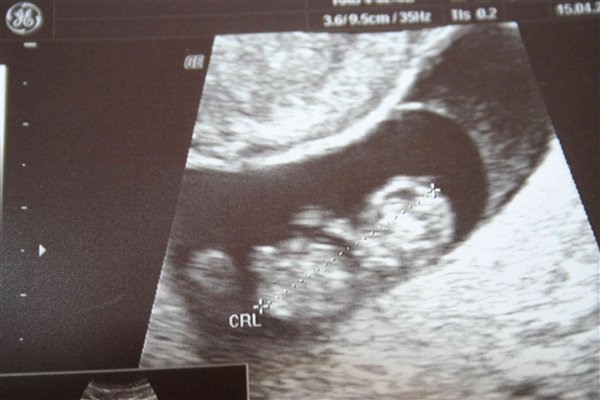

Så nåede jeg over mit "kritiske punkt" 9+1 og var til en sort/hvis scanning til 300 bobs i dag! Jeg så og hørte hjertelyd og en lille hånd der fyrede rundt

Billedet er ret ringe, men i får det lige alligevel

Birgitte 9+4